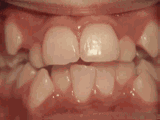

第三種

前牙移位,因?yàn)橛醒例X缺失,導(dǎo)致相鄰牙齒開始沒有秩序的亂移動,經(jīng)過矯正后是這樣的~